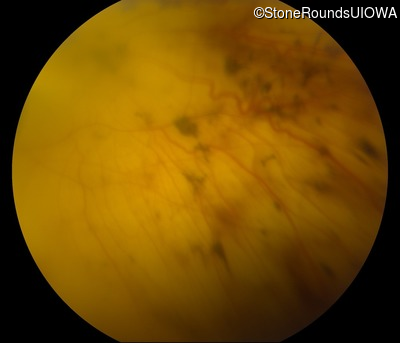

Fundus Photography - Left - 20/2000 sc

Exemplar